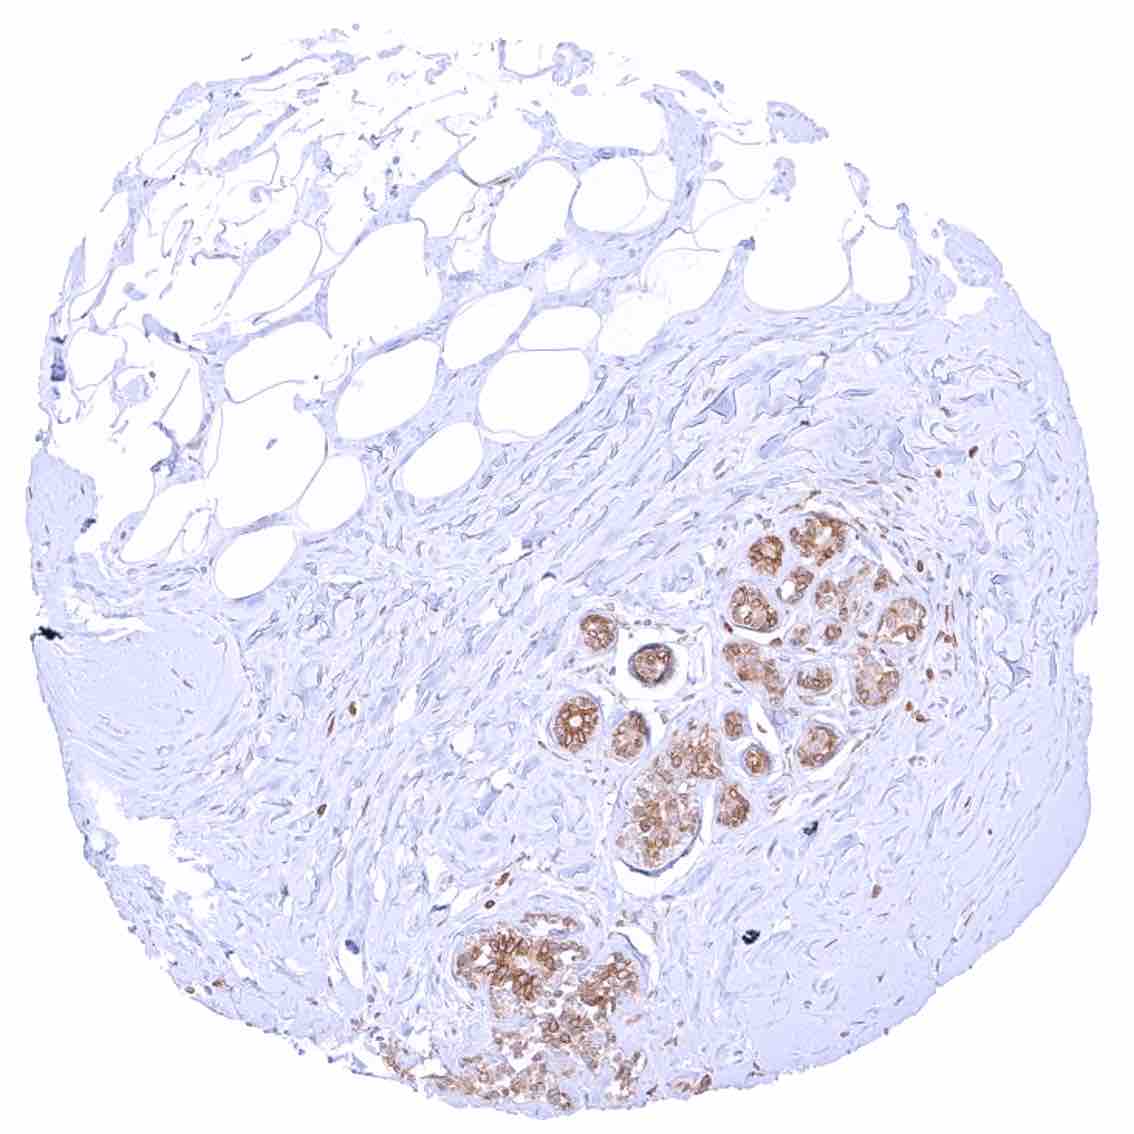

Breast – Distinct cytoplasmic bcl-2 staining of epithelial cells with higher intensity in acinar than in myoepithelial cells.